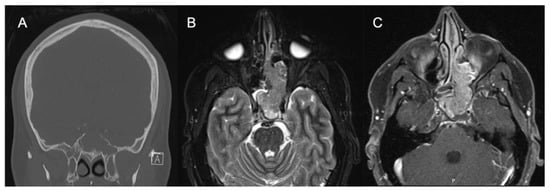

Abstract

3. Imaging